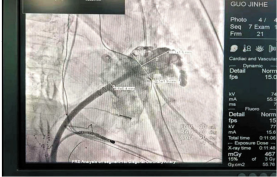

DSA下测量心耳开口大小

此次病例患者郭某,男,61岁,因“间断胸闷、气短1月余,加重1周”之主诉入院,既往有心房颤动2年。王洪涛教授接诊患者后,综合评估患者的病情,因患者CHADS2评分大于2分,属血栓高危人群,因此建议患者行房颤射频消融+左心耳封堵一站式手术。王洪涛教授采用OCE方案,首先应用STSF导管进行高效消融,提高消融效率及安全性,更少的盐水灌注使房颤合并心衰患者亦能平安完成消融。接着采用辅助vizigo可视化可调弯鞘增加导管到位几率并大幅降低X曝光,几乎实现零射线全程消融。最后用心腔内超声(ICE)指导进行实现精准的左心耳封堵手术。该方案为房颤射频消融的新技术、新理念。